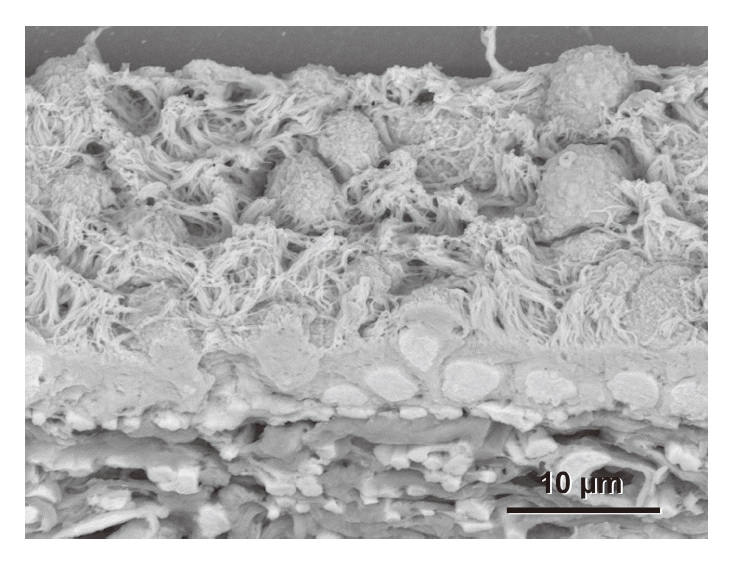

All of the electron microscopy samples described so far were fixed using a standard half-strength Karnovsky's fixing fluid(2 % paraformaldehyde + 2.5 % glutaraldehyde). Standard histopathology specimens, however, are normally fixed using a 10 % formalin solution(4 % paraformaldehyde alone). Figure 7 show a scanning electron microscopy image of rat bronchioles fixed using this solution. The image clearly shows the elaborate architecture of the ciliated epithelium and collagen fibers with a crisscrossed, layered structure. This demonstrates that our protocol is suitable for observation of histopathology specimens.

Fig. 7 Rat bronchioles fixed using 10 % formalin solution(4 % paraformaldehyde alone), which is typically used to fix histopathology specimens for light microscopy. The micrograph clearly shows the elaborate architecture of the ciliated epithelium(top) and collagen fibers with a crisscrossed, layered structure(bottom). Section thickness: 20 μm.